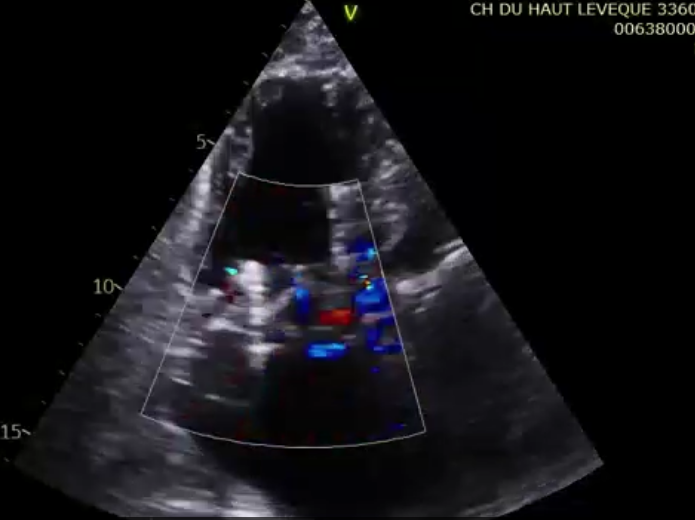

術(shù)后超聲提示微量瓣周漏